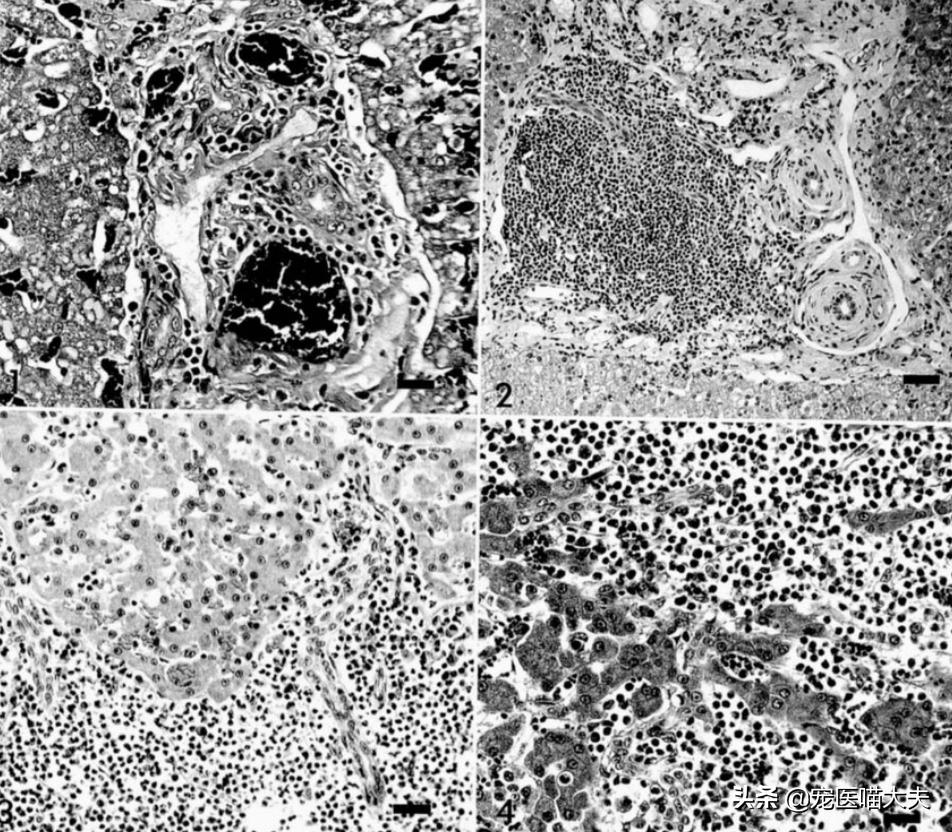

猫肝炎病理细胞

就目前而言,通过肝脏炎症的不同病理变化,将猫肝炎分为了两类,即胆管肝炎和淋巴细胞性门静脉肝炎;胆管肝炎因其发展速度又可分为慢性胆管肝炎和急性胆管肝炎;虽然都是以肝脏炎症为主要病理变化,但是在治疗中会有一定差别。

1.1 急性胆管肝炎的特征在于大量嗜中性粒细胞会浸润到肝脏的门静脉区域和胆管中,当门静脉被破坏后,就会导致邻近门静脉区域的肝细胞逐渐坏死和中性粒细胞逐渐进入到肝小叶中;急性胆管肝炎可能以胆道内的上行细菌感染而开始,比如拟杆菌、放线菌、大肠杆菌以及α溶血性链球菌等;同时胆道系统的先天性或后天性异常(比如胆结石或解剖结构异常)也会导致胆管肝炎的发生。

1.2 慢性胆管肝炎可能就是急性胆管肝炎的后期阶段,其主要特征就在于门静脉区域会和由中性粒细胞、淋巴细胞与浆细胞的组合而发生胆管混合炎性浸润,它与急性胆管肝炎不同之处就在于胆管肥大和门静脉纤维化是比较突出的,且在最后阶段,慢性胆管肝炎还可能会发展为胆汁性肝硬化,也称为“硬化性胆管炎”。

2、淋巴细胞性门静脉肝炎

淋巴细胞性门静脉肝炎也不同于急性或慢性胆管肝炎,其主要特征就在于淋巴细胞和浆细胞浸润到门静脉区域,而不是嗜中性粒细胞浸润到门静脉区域,也不会渗入到胆管中;它也存在可变程度的胆管肥大和门静脉区域纤维化。